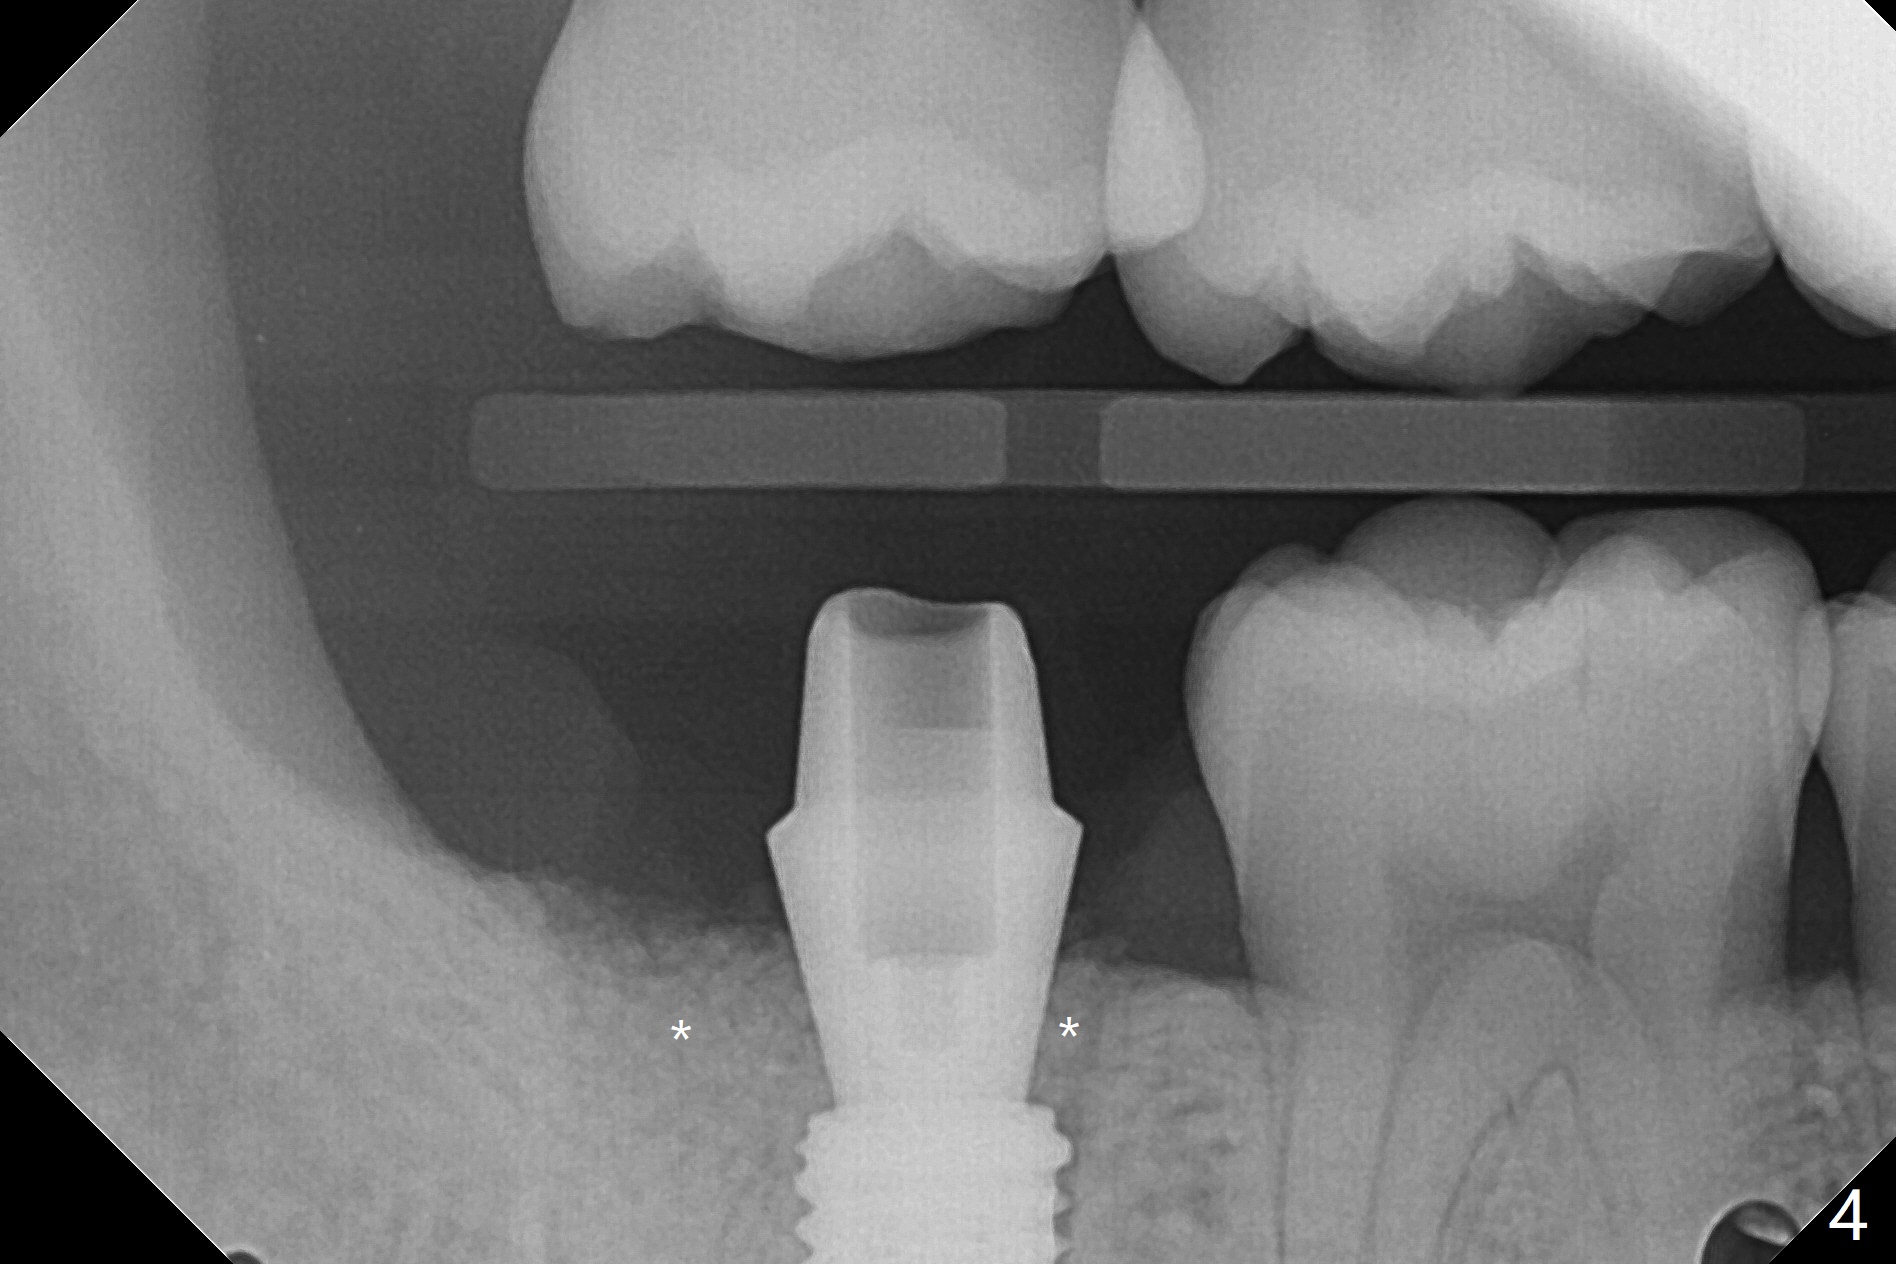

考虑到31号牙严重骨质吸收尤其是远中窝根尖(图一:*),实验室建议钻洞直径要比植体小三号(3.5毫米钻头;5.0毫米植体),其实行不通,使用4.0毫米钻头后,勉强植入4.5毫米报废植体(图一),阴差阳错:植体进入近中牙槽窝,植体四周都有骨壁包绕,包括远中:中隔(S)。最后为了使用5x11.5毫米植体,必须用4.5毫米钻头和5毫米皮质骨攻螺纹(到第三格,多3毫米,图二);放置基台好像没有就位。使用6毫米profile drill(好像去除舌侧中隔)后,手感基台就位,但是根尖片显示(图三)与图二没有区别(植体太粗,看不清楚植体与基台接触)。放置粘性骨粉后(图四),制作临时牙冠,放置PRF后,衬里多次增加固定和与牙龈密合度。术后医嘱包括手术区不使用水牙线。术后一周复诊询问骨粉游出问题。如果第二下磨牙种植能够进入近中窝,不必使用导板,4.5毫米足够,X光片观察基台就位也容易。术后三个月骨粉好像转变成正常骨质(图五,六, 30 Ncm)。